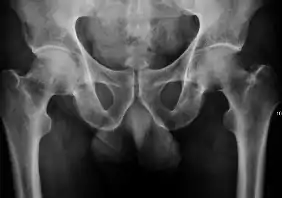

Radiological signs of transient osteoporosis of the hip include localized osteoporosis of the femoral head and neck (Figure 8). Nevertheless, final diagnosis has to be made with MRI to differentiate it from avascular necrosis and from insufficiency or stress fractures of the femoral head or neck. In case of AVN, radiographs can only demonstrate delayed or advanced signs. Staging according to Ficat classification ranges between normal appearance (stage I), slight increased density in the femoral head (stage II), subchondral collapse of the femoral head with or without “crescent” sign (stage III), and advanced collapse with secondary osteoarthritis (stage IV). In the case of stress or insufficiency fractures X-ray sensitivity has been proven to be much lower than MRI, which is currently the gold standard.[1]

Figure 8:

X-ray of a patient with transient osteoporosis of the left hip showing osteoporosis.[1]

Coronal stir imaging in transient osteoporosis, showing diffuse edema.[1]

Scintigraphy (A), sagittal T1 (B), and coronal PD fat sat of a patient with a subchondral fracture of the femoral head with convex shape to the articular surface.[1]

Coronal T1 of a patient with avascular necrosis of the femoral head.[1]